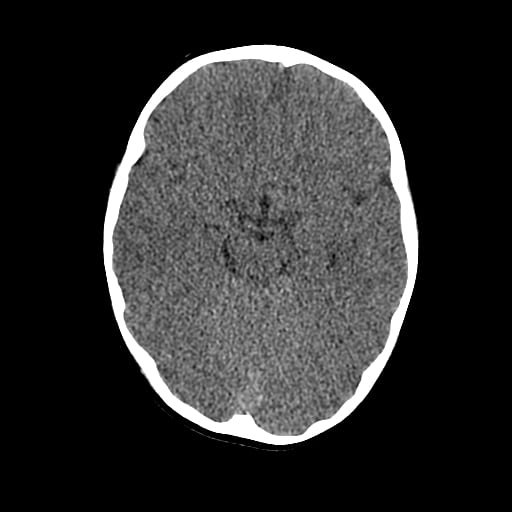

Age: 1

Sex: Male

Indication: Fall